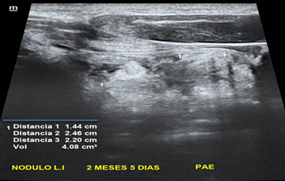

CASO: Paciente masculino de 74 años de edad con antecedentes de hipotiroidismo en tratamiento con levotiroxina de 88mcg al día, a la valoración ecográfica presenta imagen mixta, con vegetaciones hacia polo inferior y tabique transverso hiperecogénico completo con componente quístico 70% (1p) - isoecogénica (1p) - bordes bien definidos - más ancha que alta - no calcificaciones, total 2 puntos (TI-RADS 2) - mide 2.8 x 3.6 x 3.7 cm, volumen 20.61 ml, ligera vascularidad perinodular.

Paciente sometido a inyección percutánea con etanol en donde se evidencia una disminución considerable del volumen nodular, a los 2 meses 5 días se evidencia un volumen 4.08ml con una taza de éxito del 80.21%

Imagen 2. Nódulo mixto post ablación etanol

Fuente: Elaboración Propia